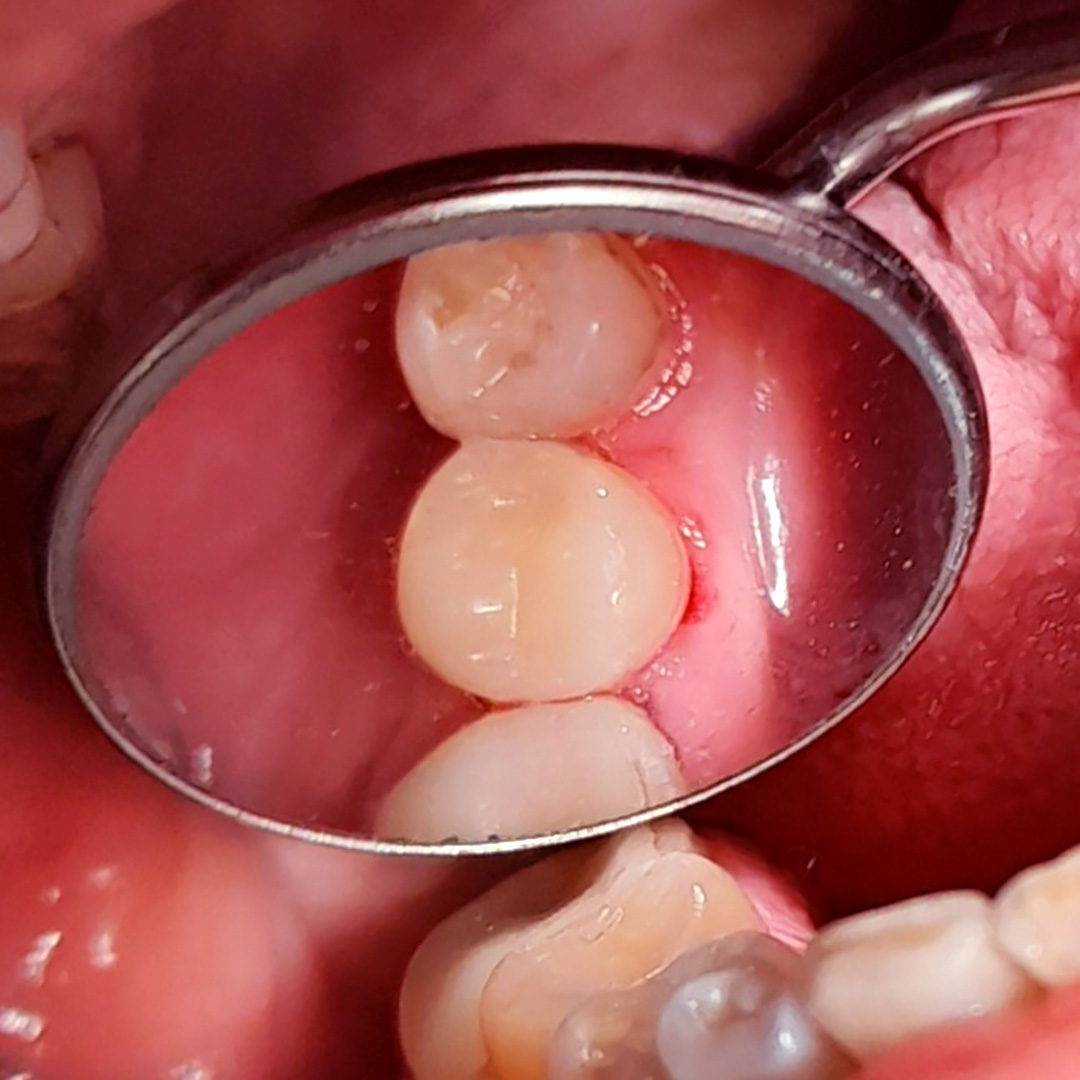

До и после лечения

В «Стоматологию Комфорта» обратился пациент с жалобами на выпадение пломбы из 45 зуба и кратковременные боли от приёма холодных продуктов. Врач-стоматолог-терапевт Похилько Н. Г. в ходе осмотра выявила кариозную полость на мезиально-окклюзионно-дистальной поверхностях 45 зуба. Зондирование было болезненно, перкуссия — безболезненна. Был поставлен диагноз: хронический глубокий кариес 45 зуба. Врач пришёл к выводу о лечении с последующей установкой пломбы из светоотверждаемого композита Estelite.

В ходе лечения проведены следующие работы:

- введение инфильтрационного анестетика;

- препарирование кариозной полости под контролем кариес-маркера;

- медикаментозная обработка;

- наложение лечебной прокладки;

- наложение изолирующей прокладки;

- постановка пломбы из композита Estelite;

- шлифовка и полировка пломбы;

- обработка полости рта.